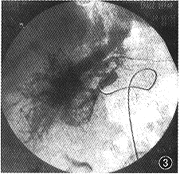

图3 肝动脉DSA示肝右动脉增粗,肝静脉增粗,远侧可见畸形毛细血管团影